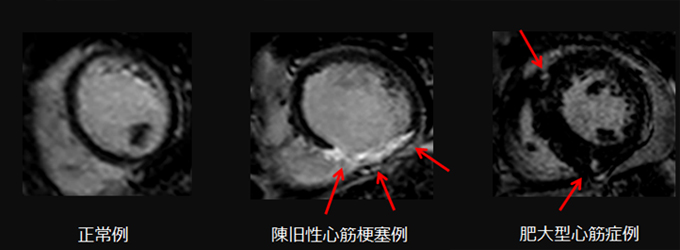

心臓疾患のCTとMRI 第2版 | 佐久間肇, 陣崎雅弘, 北川覚也, 石田。心臓疾患のCTとMRI 第2版 | 佐久間肇, 陣崎雅弘, 北川覚也, 石田。心臓疾患のCTとMRI 第2版 | 佐久間肇, 陣崎雅弘, 北川覚也, 石田。「心臓疾患のCTとMRI」佐久間 肇 / 陣崎 雅弘 / 北川 覚也 / 石田 正樹定価: ¥ 14000 裁断済み商品です。放射線医学センター (放射線科) | 診療科・部門紹介 | 東京西。中身に書き込み等ありません。新・徒手筋力検査法 第10版 コード未使用。スキャナできれいに取り込むことができました。神経内科ハンドブック 鑑別診断と治療(裁断済み)。スキャンに伴うページのよれが多少ございます。ガイトン生理学 第13版 John E. Hall。裁断済みのため商品の状態は傷や汚れありとしています。薬ゼミ 100日インプットマスター ぎゅっと一問一答集 9教科 薬剤師国家試験。